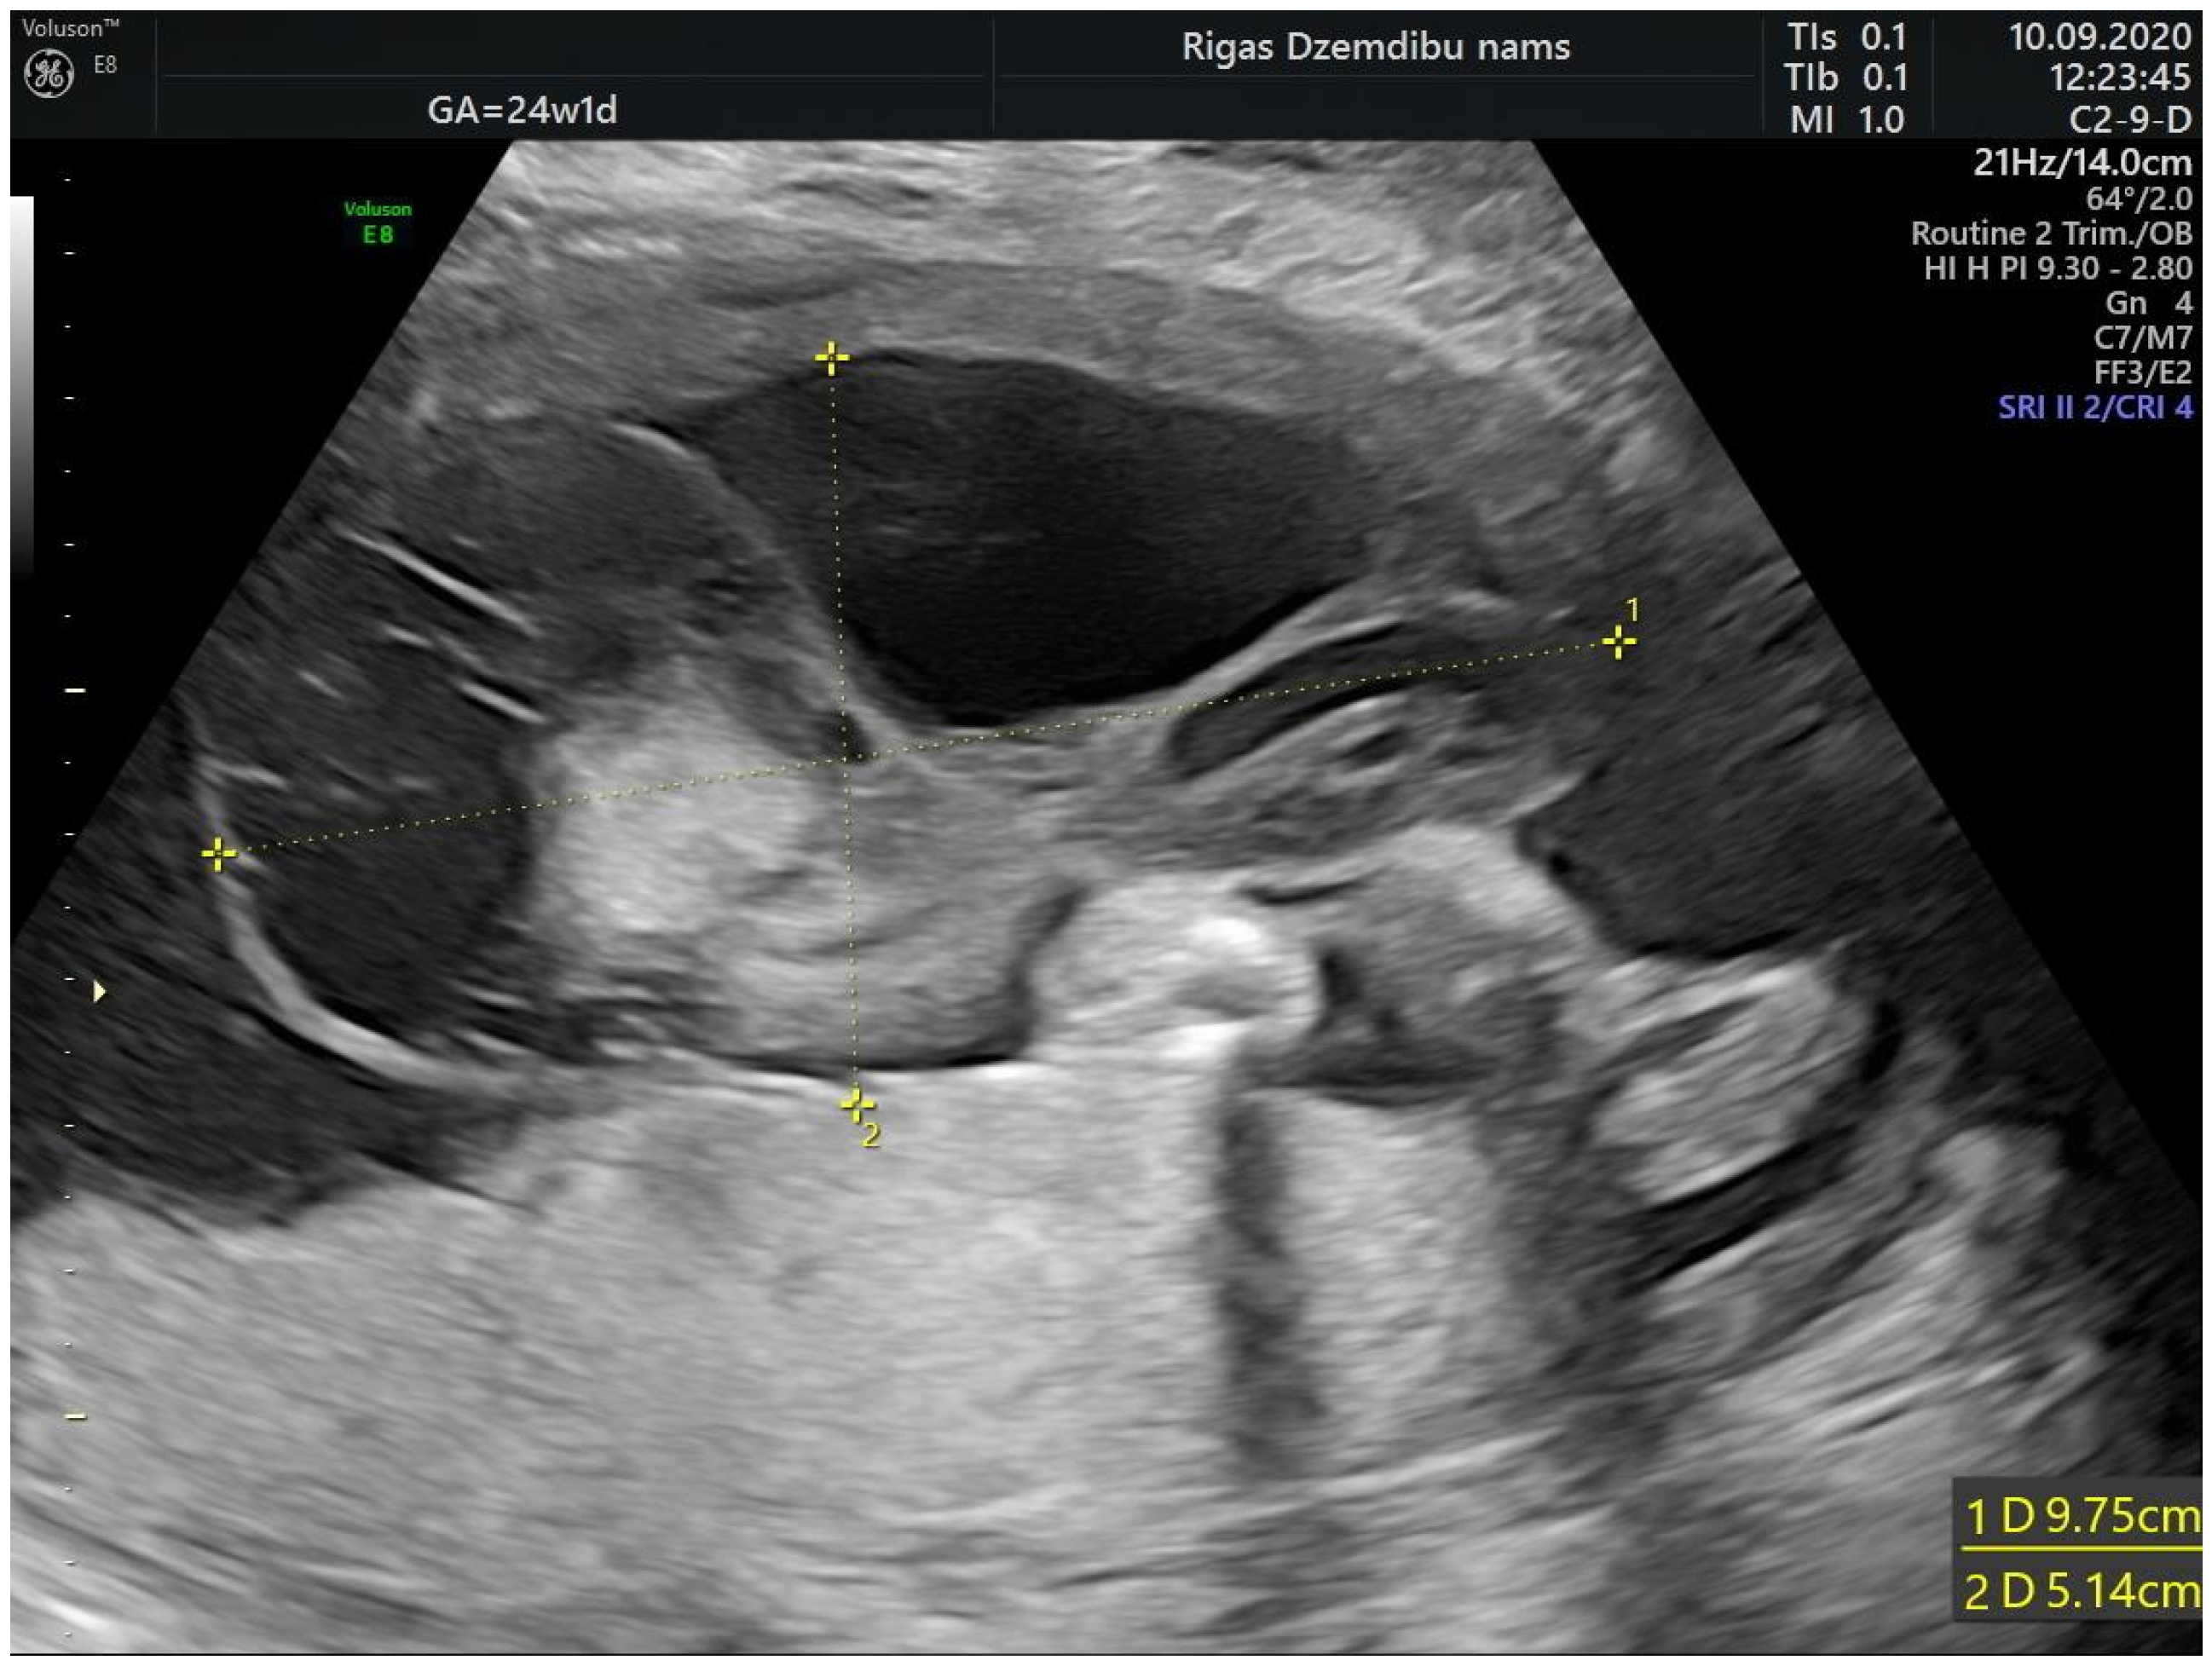

A 28-years-old woman, gravida 2, para 1, was referred to Riga maternity hospital Fetal medicine unit for the second opinion at 24 weeks of gestation. Woman had previously vaginal delivery, complicated by manual placental ablation. She had an otherwise uneventful medical history and denied smoking, use of alcohol, illicit drugs or medications. Detailed ultrasound examination showed a single anatomically normal fetus, with appropriate for gestational age biometric measurements. During the examination the multilocular solid tumor measuring 9.6 × 7.8 × 6.7 cm (265.993 cm3) at the middle portion of the umbilical cord was observed (Figure 1). The differential diagnosis comprised umbilical cord teratoma and angiomyxoma.

Figure 1.

Tumor appearance at 24 + 1 weeks.